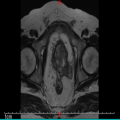

| 影像学检查:(点击查看大图) | 平扫:前列腺区见多发结节融合成团状异常信号,形态不规则、局部呈菜花状改变,边界欠清,范围约61mm×34mm×64mm,病变在T1WI上呈等信号,在T2WI上信号不均匀,呈等信号内见不规则团片状稍高信号,周围脂肪间隙模糊,病变与双侧精囊腺、膀胱后壁、直肠后壁、左侧闭孔内肌分界不清,直肠下段前部脂肪间隙消失,左侧精囊角消失;膀胱充盈欠佳,膀胱壁不规则稍增厚,最厚径约7mm。盆腔、双侧腹股沟、髂血管旁区见多发肿大淋巴结,较大大小约22mm×14mm。 增强:前列腺区见病变呈不均匀轻度环形强化,病变侵犯邻近直肠,相应肠管管壁增厚呈类似强化;盆腔、双侧腹股区、髂血管旁区肿大淋巴结呈轻度不均匀强化。增厚膀胱壁呈明显强化;余未见异常强化表现。 与2023-09-23 前列腺MRI对比:前列腺癌术后改变,前列腺区见多发结节融合成团状异常信号,新见左侧闭孔内肌、直肠后壁受累,左侧精囊角消失,髂血管旁区见多发肿大淋巴结,盆腔、双侧腹股沟淋巴结较前稍增多,其余所见大致相仿。 影像诊断意见: 前列腺癌(UICC分期:T4N1Mx IV期),双侧精囊腺、膀胱后壁、直肠后壁、左侧闭孔内肌受累,盆腔、双侧腹股沟、髂血管旁区见多发肿大淋巴结,复查病变较前进展。 |